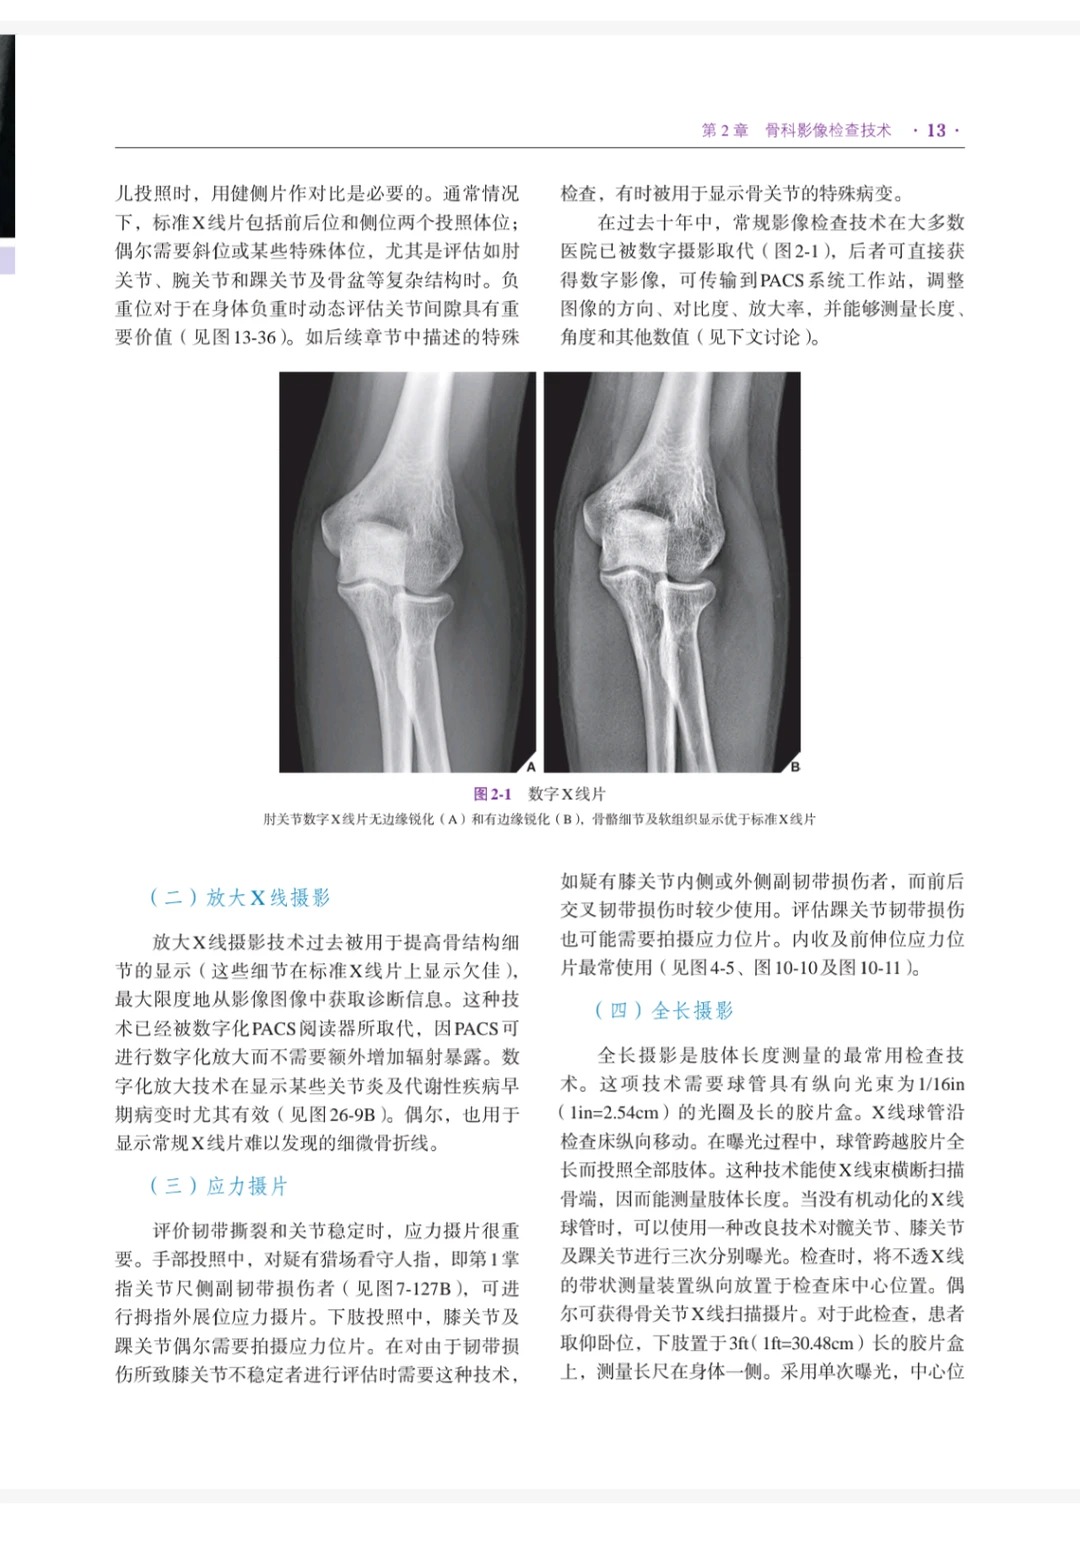

1. 超清画质+完整目录,查阅效率拉满:超清电子版PDF,完美还原书籍原貌,各类骨科影像图、示意图、病例图像清晰可见,细节无模糊,便于精准解读影像特征;自带完整目录,可快速定位33章内容,不用逐页翻找,临床查阅、学习复盘省时省力,彻底解决“找知识点难、阅片不清晰”的核心痛点[1][3]。

2. 内容全面,覆盖骨科影像全场景:全书共7篇33章,内容包罗万象,既有骨科影像学基础理论的系统论述,又有大量高清图表和临床病例图像,涵盖关节造影、穿刺活检、创伤、运动医学、关节炎、骨肿瘤、感染、代谢性骨病变、内分泌疾病、系统性疾病及发育异常等各类骨科相关疾病的影像学特征、诊断和鉴别诊断,一站式满足临床诊疗、影像解读、专业学习等多元需求[1][2][3]。